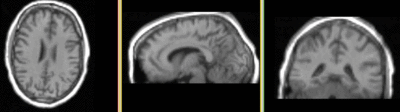

this is the fixed reference image. All images are aligned into this space this is the fixed reference image. All images are aligned into this space lleft lleft this is the T1 moving image

fixed image

DTI

DTI baseline

moving image

T1 SPGR